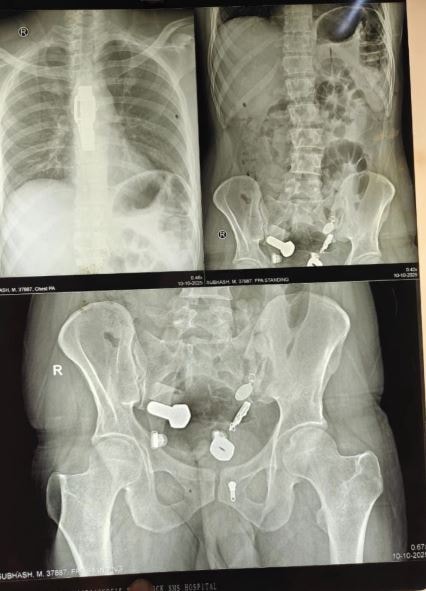

Các bác sĩ đã bị sốc khi kết quả chụp chiếu cho thấy một chiếc đồng hồ mắc kẹt trong thực quản của bệnh nhân, cùng với các mảnh sắt, đai ốc và bu lông mắc kẹt trong ruột già, theo như Need To Know đưa tin .

Hình ảnh chụp X-quang cho thấy khối vật thể kim loại kỳ lạ bên trong dạ dày của người đàn ông.